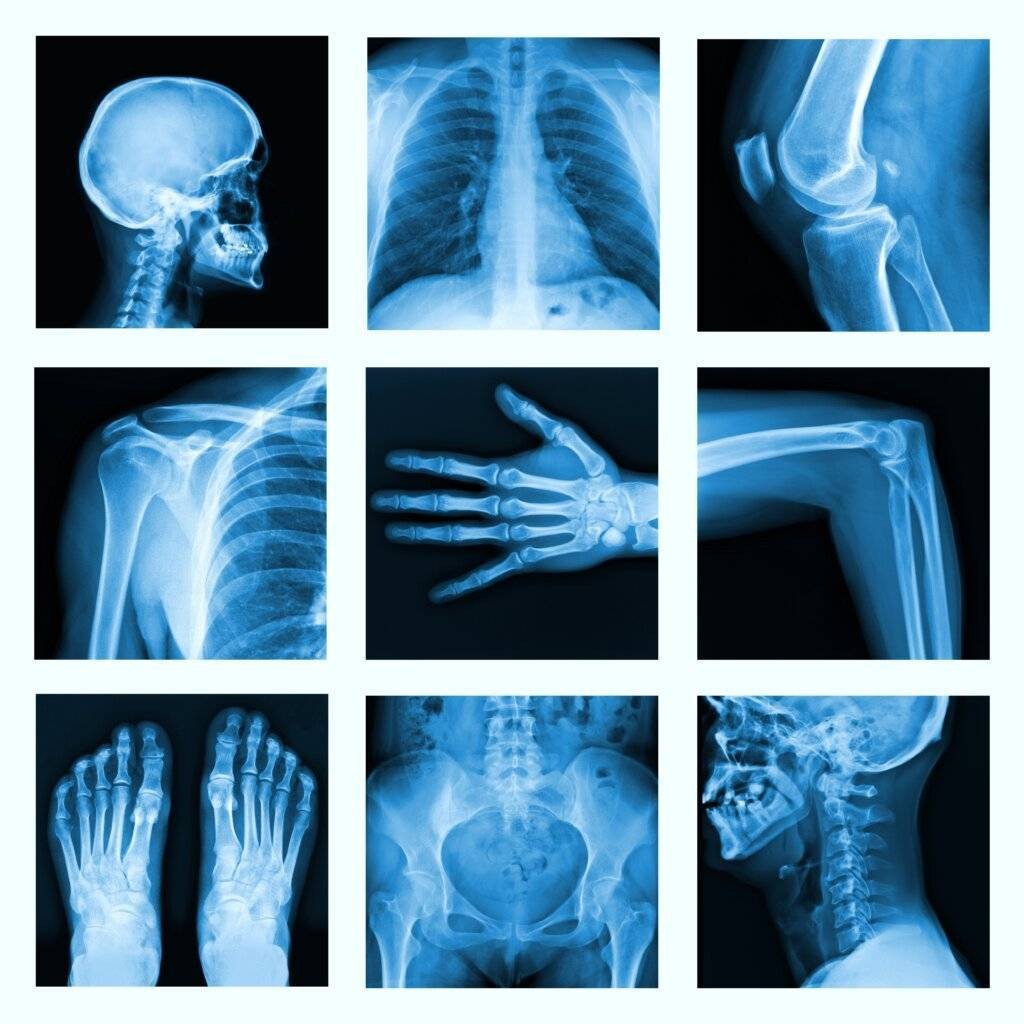

- Basics aus der Strahlenphysik und der Strahlenbiologie

- Praktische Beispiele im Strahlenschutz für den Patienten und für den Anwender